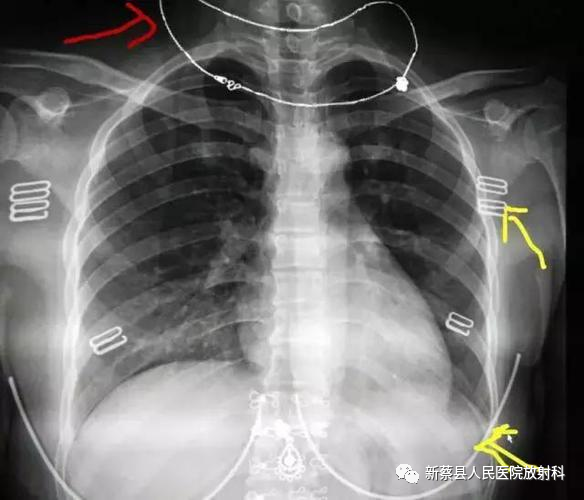

新蔡县人民医院放射科拥有医学影像室、CT室、磁共振室。经过医院和全体科室人员的共同努力,尤其是近几年高端影像设备和技术的引进,科室已发展成为集医疗、教学、科研于一体的临床平台学科。

拥有64排螺旋CT(低剂量CT)、1.5T、3.0T超导高场MR系统、数字化X线摄影系统(DR)、美国豪洛捷乳腺机、数字移动床旁机、韩国双能骨密度检测仪、互联网智能诊断及自助打印系统等设备;主要开展低剂量CT健康体检及高危人群普查、肺癌筛查、CT介入肺肿瘤穿刺活检、骨密度仪筛查骨质疏松、C型臂骨科手术应用、ICU辅助DR诊断、溶栓前急诊CT辅助诊断等项目。

放射科始终以标准化、规范化、高质量的影像为目标,实现影像清晰度高,成像快速、准确、数字化存储,既能满足“量”的需求且能保持“质”的水准。科室将继续秉承“技术优质,服务优良,关怀细微,流程快捷”的服务理念,为临床提供更多有价值的影像学检查信息,为患者提供满意的诊疗服务。